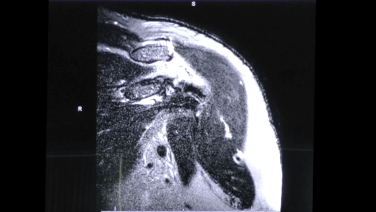

MRI & Xray Review Labral Tear Shoulder with Stephanie Muh, MD

Surgeon's approach to Reading an MRI - Stephanie Muh, MD